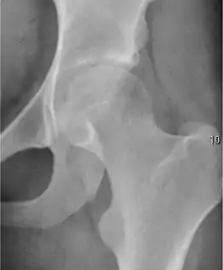

- Osteoarthritis

In adults, one of the main indications for radiographs is the detection of osteoarthritic changes (Figure 1(e)). Nevertheless, radiographs usually detect advanced osteoarthritis that can be graded according to the Tönnis classifications. The grading system ranges from 0 to 3, where 0 shows no sign of osteoarthritis. Intermediate grade 1 shows mild sclerosis of the head and acetabulum, slight joint space narrowing, and marginal osteophyte lipping. Grade 2 presents with small cysts in the femoral head or acetabulum, moderate joint space narrowing, and moderate loss of sphericity of the femoral head. Grade 3 is the severest form of osteoarthritis, which manifests as severe narrowing of the joint space, large subchondral cyst with productive bone changes that may lead to deformity of the bone components of the joint, while secondary osteoarthritis due to calcium pyrophosphate deposition can be diagnosed when calcification of hyaline cartilage and fibrocartilage is detected.[1]